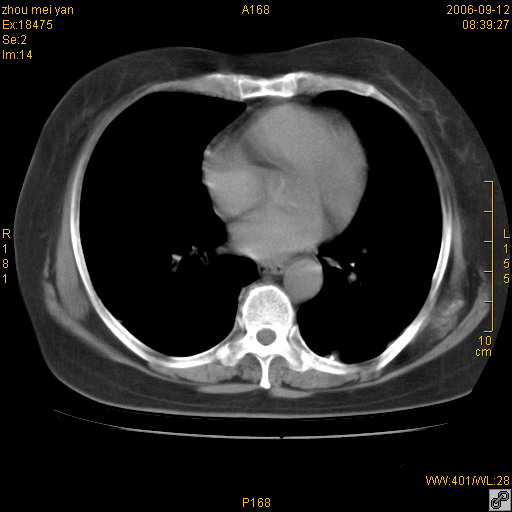

患者、女、55岁。因心率失常住院检查ct发现胸部多发结节。腹部b超肝、胆、胰、脾、肾、子宫附件未见异常。无结核病史,无粉尘接触史。请大家来会诊。谢谢!

病变位于胸膜,多发结节,边界清楚,内见小结节状钙化。其它未见异常。

双侧胸膜多发结节,形态不规则,边缘较清楚,每一个结节中心似乎都有钙化点的特征,与胸膜广基相切。临床无结核病史,无粉尘接触史。

胸膜间皮瘤可能性大。在气管隆突前可见一肿大淋巴结影。

影像表现十分有特点:双侧肋胸膜及膈胸膜广泛散在分布大小在2至6mm左右,较大病灶中心可见钙化。

双侧肋胸膜及膈胸膜广泛散在分布大小不等结节影,较大病灶中心可见钙化。